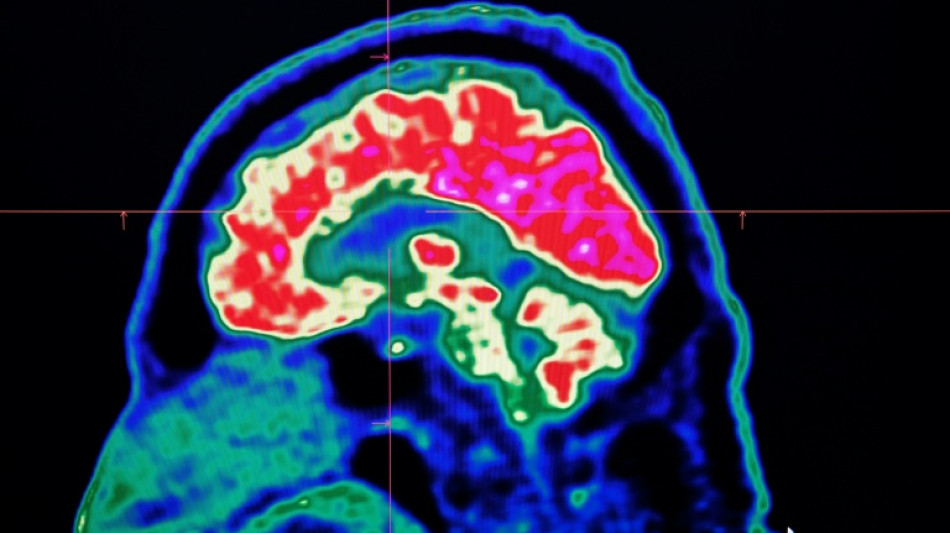

In 2021, health officials in New Brunswick launched an investigation involving 48 patients with a range of neurological symptoms but no apparent common illness. These included muscle spasms, memory loss, hallucinations and balance issues.

Some in the province of less than a million people began describing the condition as a mystery brain disease.

Provincial officials said at the time that the patient group could be suffering from a new disease not previously seen in Canada and began using the term "possible neurological syndrome of unknown cause."